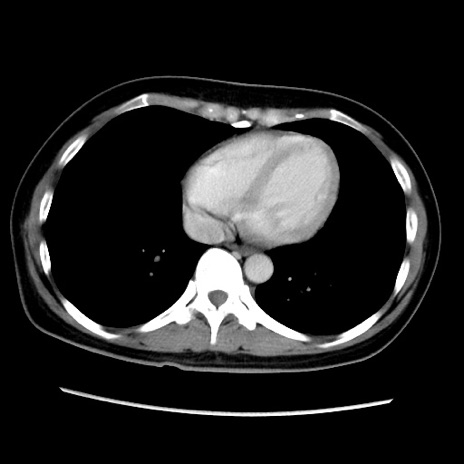

症例39(横断像)

【症例】40歳代女性

【主訴】上下腹部痛

【現病歴】2日目から下腹部痛あり。夜間は痛みで眠れなかった。昨日より上腹部痛と下痢が出現。臥位で痛みは軽快したため、休んでいた。本日になって臥位でも立位でも痛みが強くなってきたため救急要請。

【既往歴】子宮内膜症

【身体所見】部:平坦・軟、左上下腹部に圧痛あり、反跳痛あり。

【データ】WBC 21800、CRP 26.78